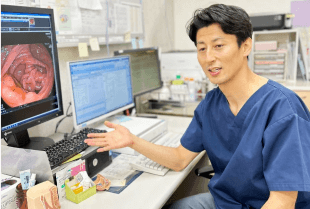

診察室にて実際の大腸カメラ画像をお見せしながら検査結果を医師より丁寧にご説明致します。また、ポリープ切除や組織検査を行った場合には、結果は後日判明いたしますため、その際には改めてご来院いただく必要がございます。